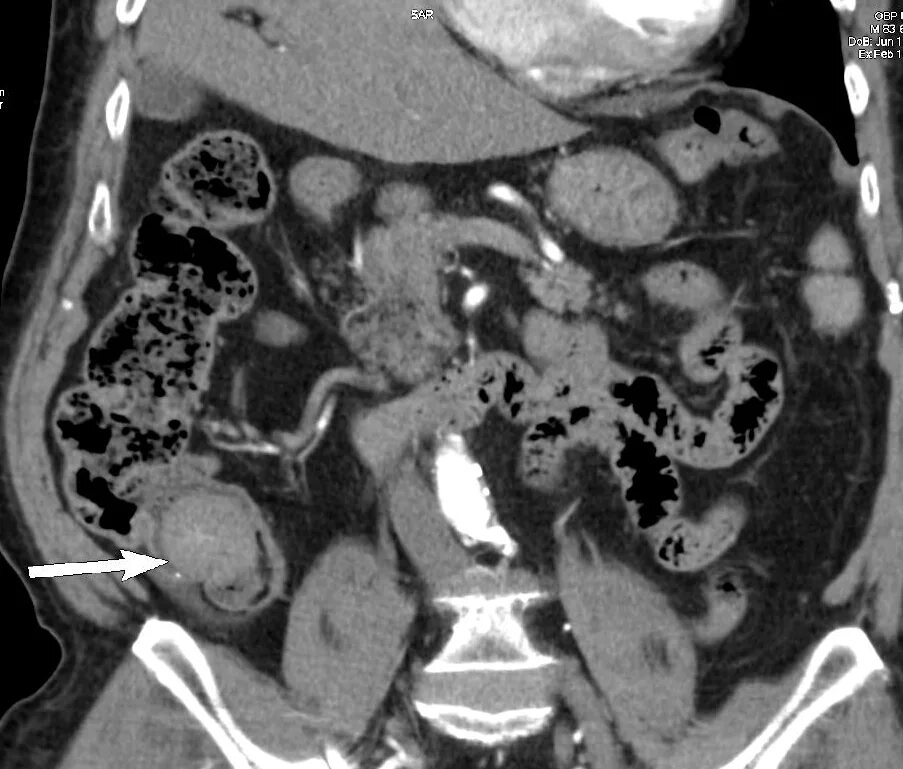

Мрт обп с контрастированием